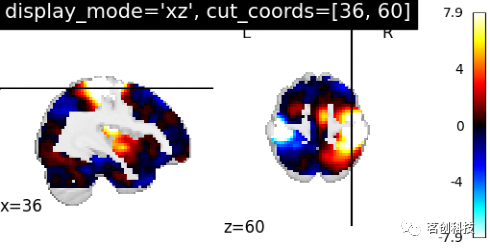

设置display_mode= 'xz',cut_coords=[36, 60],表示在x和z方向上进行切割,并且是手动定位切割。

plotting.plot_stat_map(stat_img, display_mode='xz',

cut_coords=[36, 60],

title="display_mode='xz', cut_coords=[36, 60]")